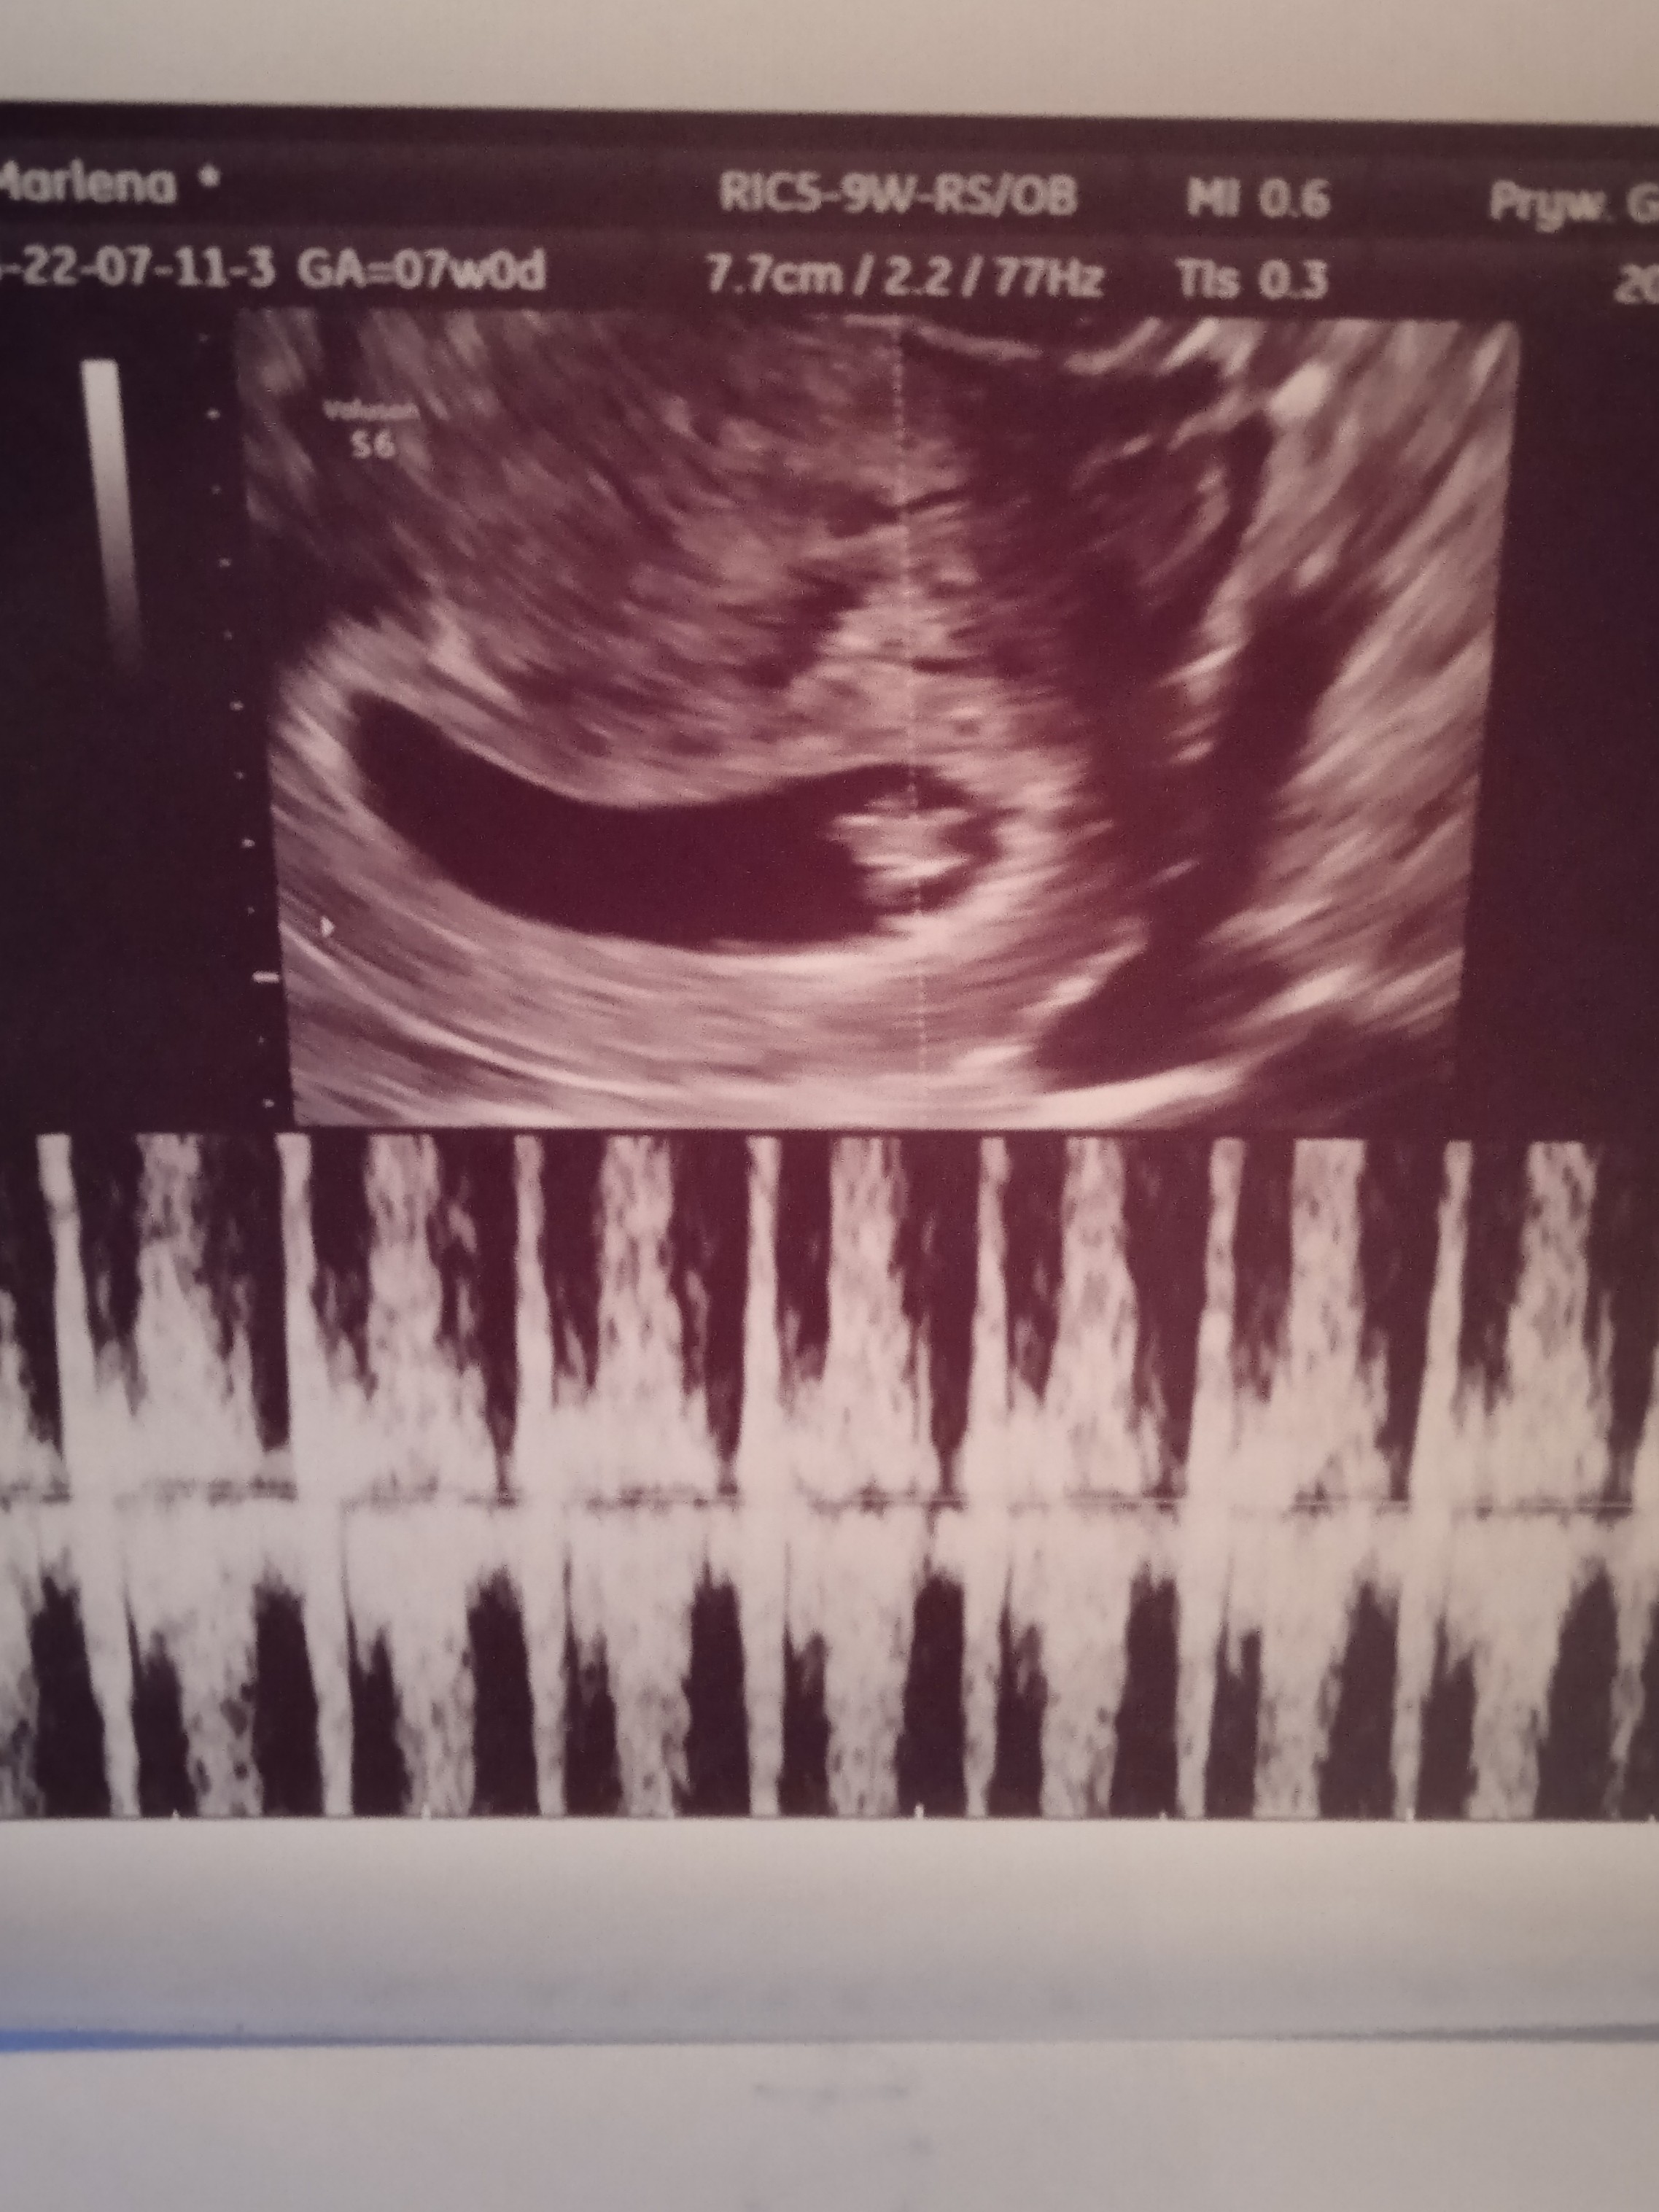

Dziewczyny ja już po wizycie😁dziś 7t0d😉Kropek ma 1.16 cm i pięknie bijące serduszko❤️

• IMG_20231120_183709.jpg

IMG_20231120_183709.jpg

823,2 KB · Wyświetleń: 117

Ale duży kropek 😍 zazdroszczę zdjęć. Ja jeszcze 12 dni do wizyty...